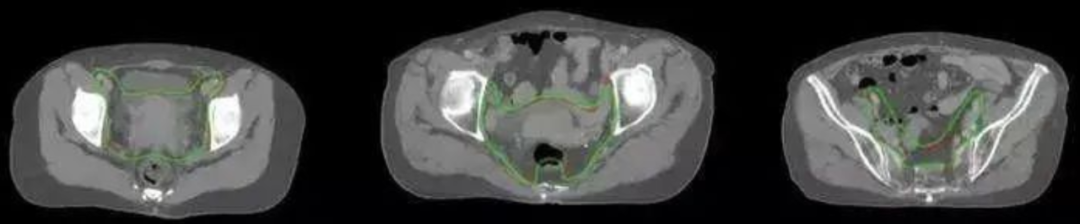

uAI智能分割引擎可以對74個主要危及器官和靶區(qū)進行分割

綠線:自動勾畫效果 紅線:醫(yī)師手動勾畫效果

目前,uAI放療輪廓勾畫軟件可實現(xiàn)亞秒級智能分割靶區(qū) —— 全盆腔淋巴引流區(qū)和宮旁區(qū)域,經(jīng)醫(yī)師檢查確認后到勾畫完成只需2-3分鐘。